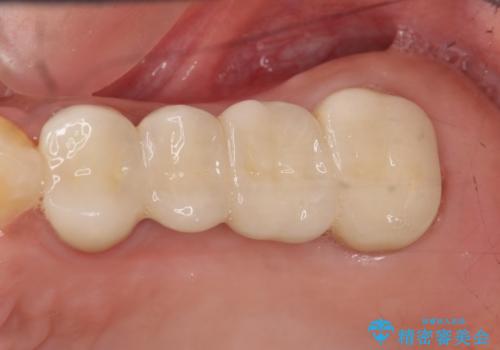

![[親知らずの移植] インプラントを用いない咬合回復の症例 治療後](https://seimitsushinbi.jp/wp/wp-content/uploads/2017/09/609c83174eb270ca046e1500a1298cd6-500x350.jpg)